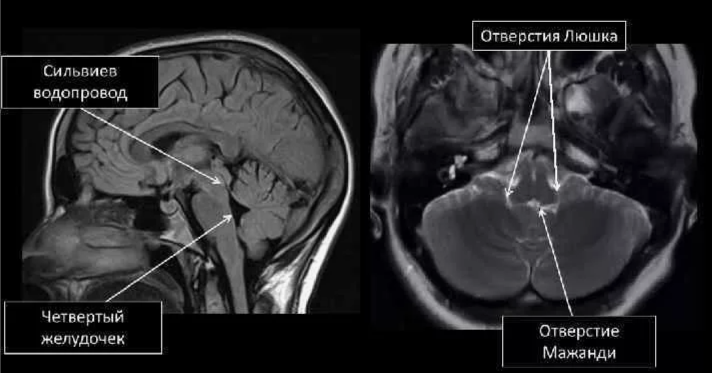

Отверстия Люшка и Мажанди - это отверстия в полости IV желудочка мозга, через которые имеется сообщение ликвора с субарахноидальным пространством. Отверстие Монро соединяет каждый боковой желудочек с III

Краткая схема ликвороциркуляции

В норме из боковых желудочков мозга ликвор через отверстие Монро поступает в III желудочек, оттуда по водопроводу в IV желудочек, через отверстия Мажанди и Люшка - в подпаутинное пространство мозга. Последние в области основания мозга формируют ряд базальных цистерн, из которых ликвор поступает в конвекс, омывая полушария головного мозга.